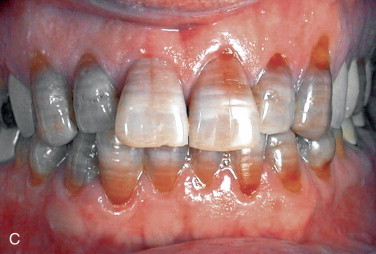

What causes this?

Tetracycline taken by the mother during pregnancy